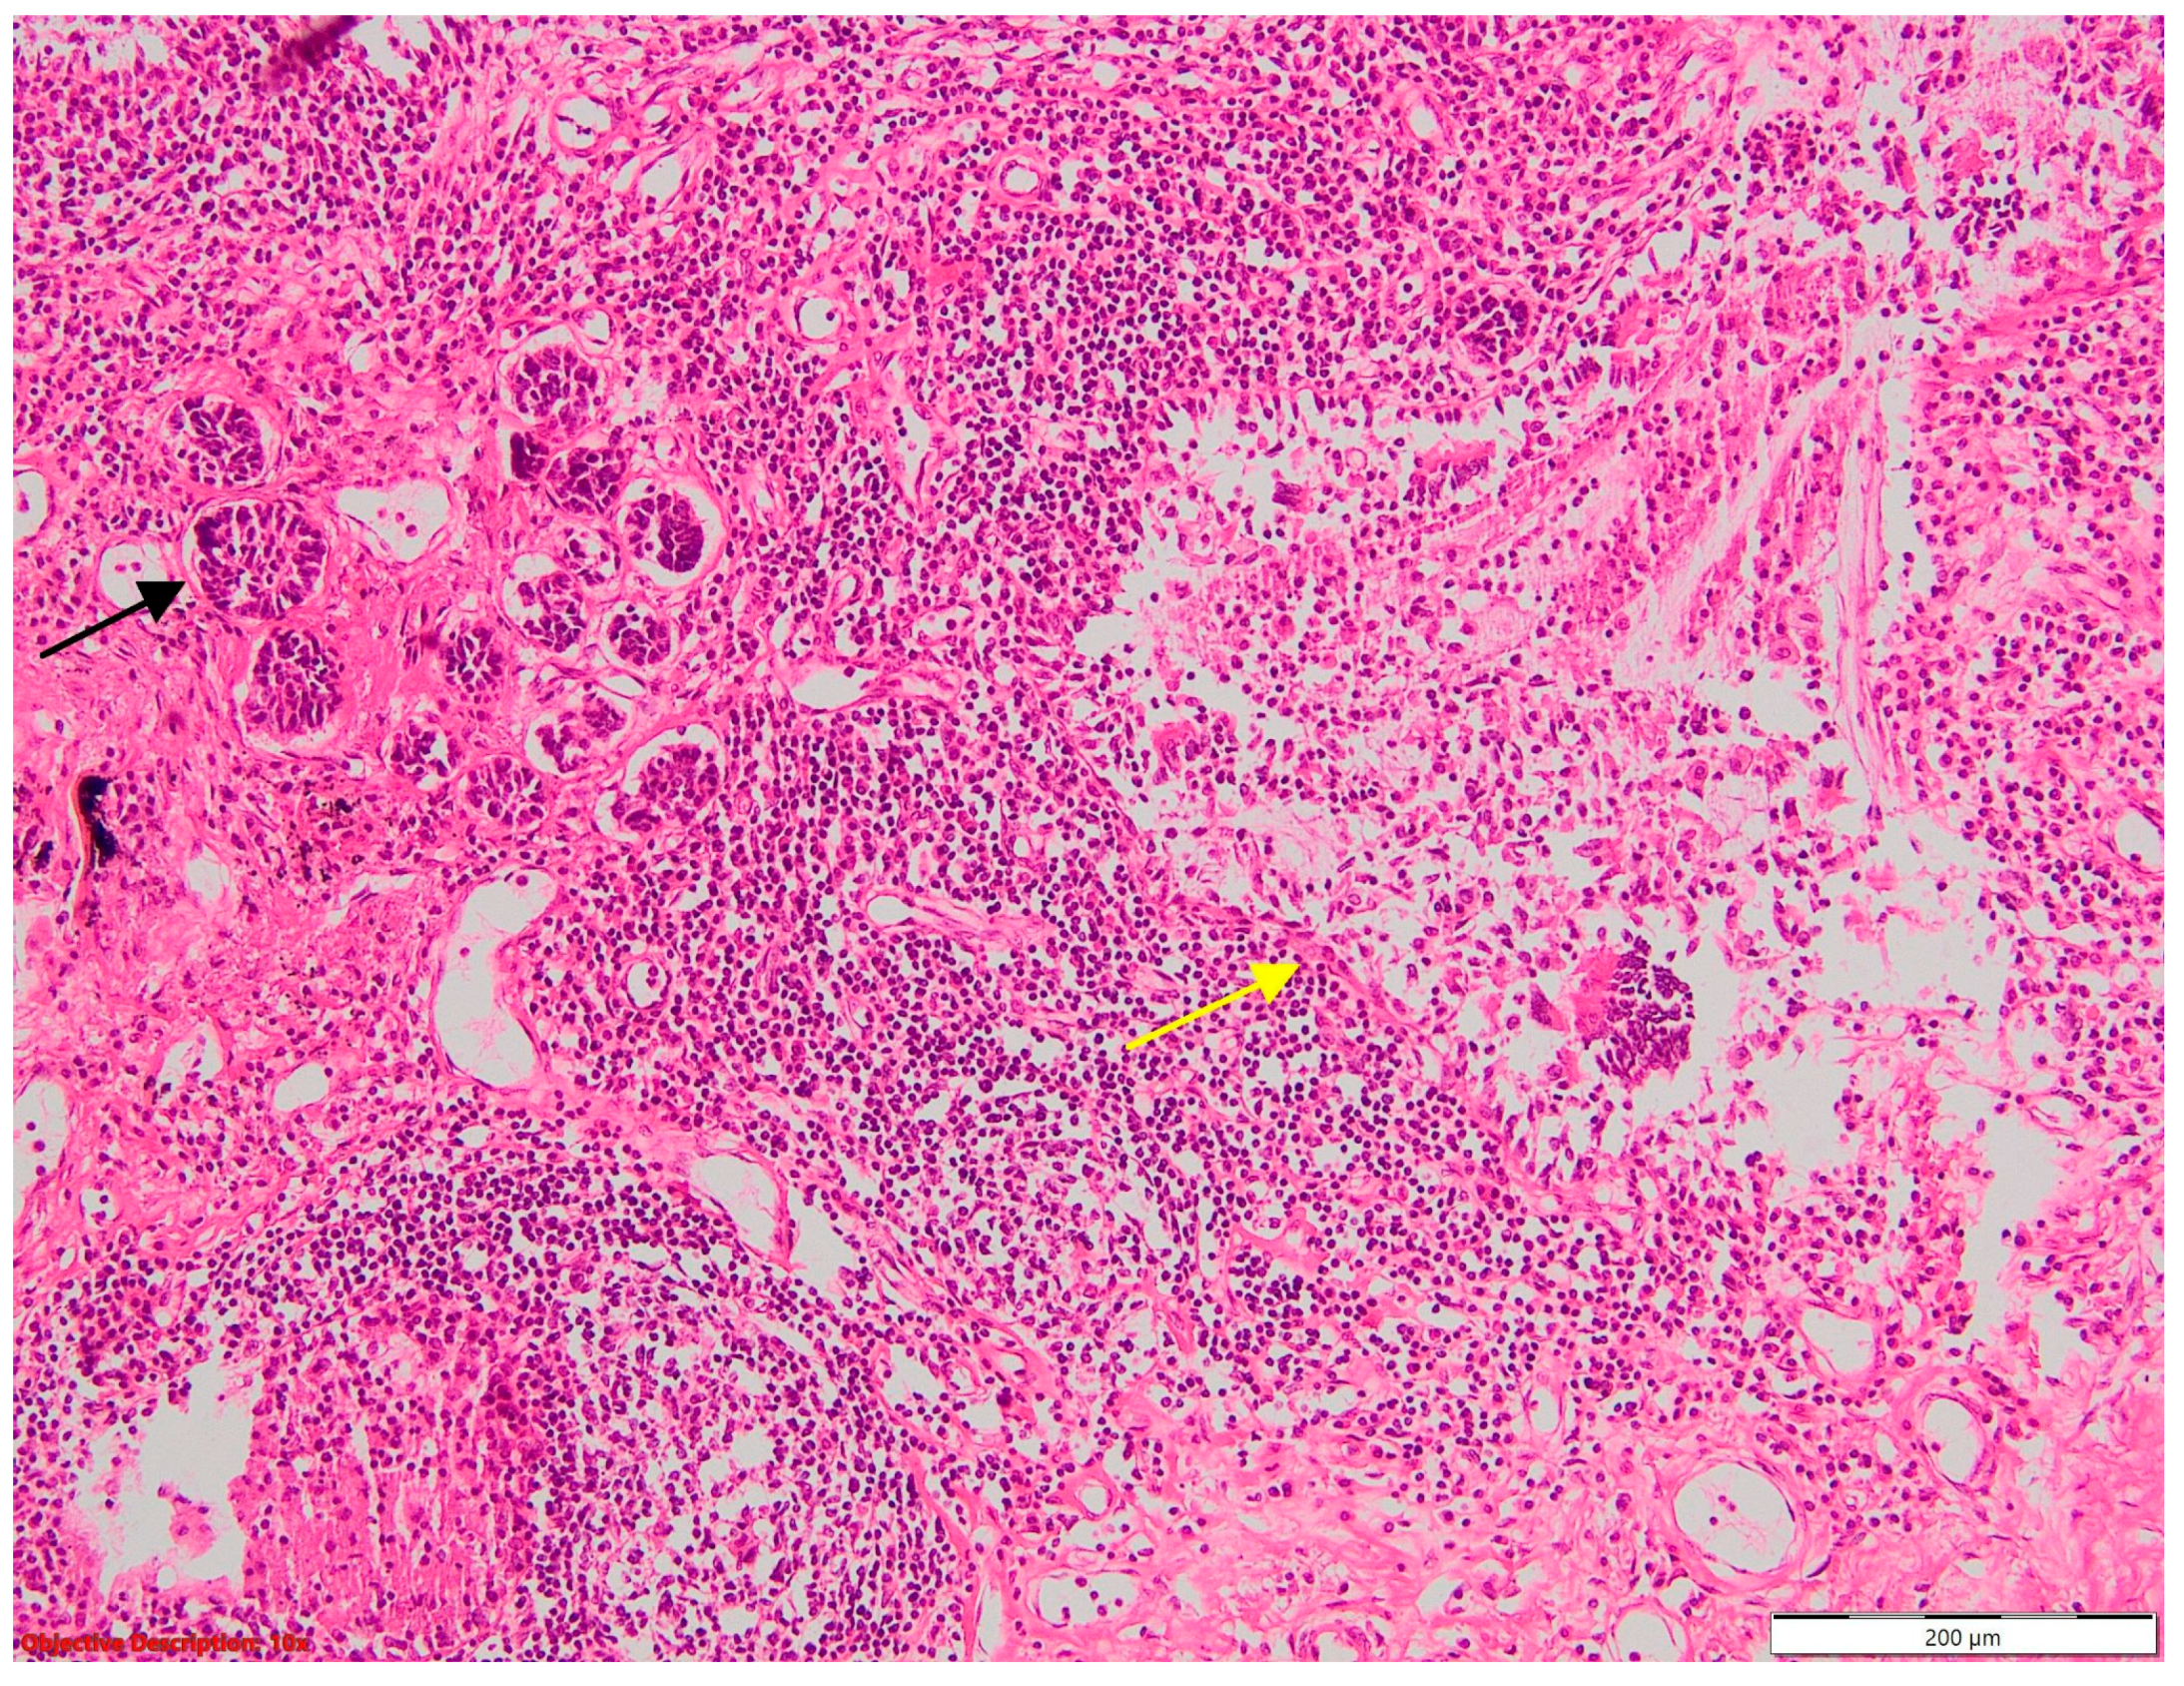

Figure 14. Tumorlet—clusters of neuroendocrine cells (→) are present adjacent to a bronchiolar structure, with detached epithelium (); significant inflammatory infiltrate; HE, 100×.

Tumorlets (Figure 14) were associated with adenocarcinoma in one case and another case with typical carcinoid (Figure 15) and sarcoidosis.